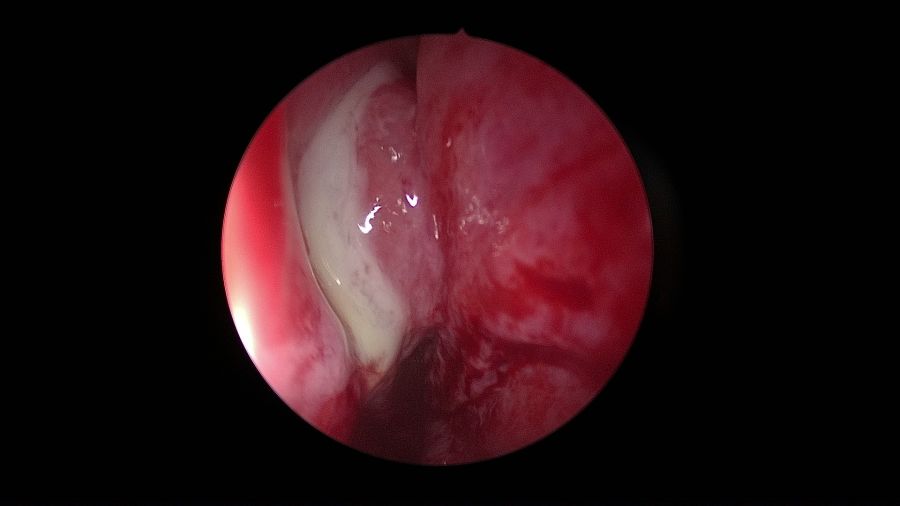

El pus en el meato medio (66-8%), seguido del edema del meato medio (34-43%) y pólipos (12-34%) han sido los hallazgos endoscópicos más comúnmente informados en la SO en diferentes estudios26 (Figura 2).